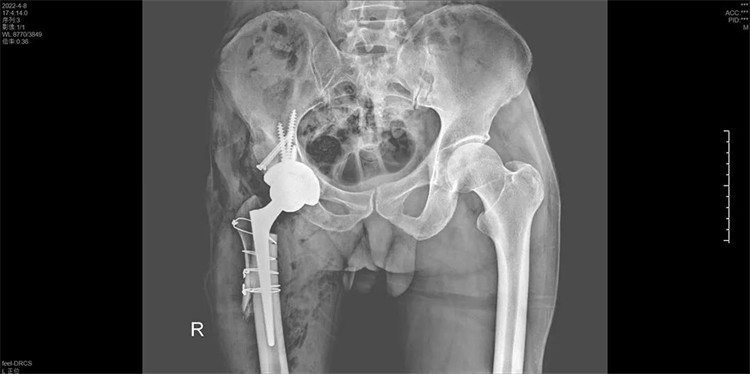

手術(shù)過(guò)程一氣呵成,手術(shù)歷時(shí)2個(gè)小時(shí),出血200ML,順利地為周大伯進(jìn)行了右側(cè)人工全髖關(guān)節(jié)置換術(shù),將人工髖關(guān)節(jié)準(zhǔn)確地安裝在周大伯的真臼內(nèi)并做了牢固的固定。術(shù)后第1天周大伯就已下地行走。